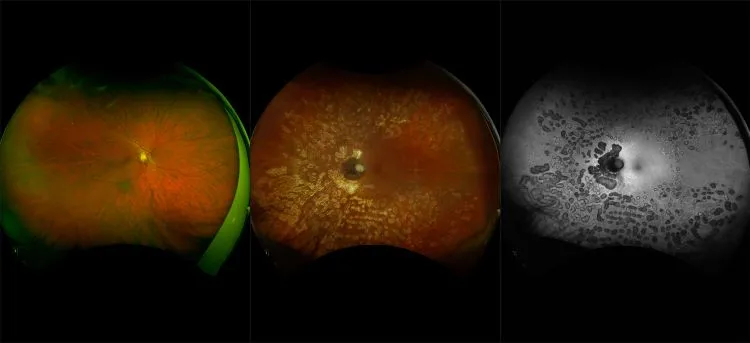

optomap® Recognizing Pathology

This material is designed as a searchable reference resource to support clinical decision-making. The information contained here should be used as general guidance when viewing optomap and OCT images from Optos devices. The differential diagnosis should be made under the direction of the responsible physician. These images were taken on the latest ultra-widefield optomap devices.

The Cases and Images

optomap Recognizing Pathology is searchable by pathology and/or optomap image modality. You may search by multiples of each selection. Each individual case is represented by the accompanying thumbnail image. Most cases include several different optomap image modalities. To view a full description of the case, please click on the thumbnail. Each image in the case will be made available through our OptosAdvance software which provides multi-dimensional visualization of digital images to aid in the analysis of anatomy and pathology. Support and pathology definitions can be found by selecting one of the buttons, above. Should you have questions, please complete the form below.